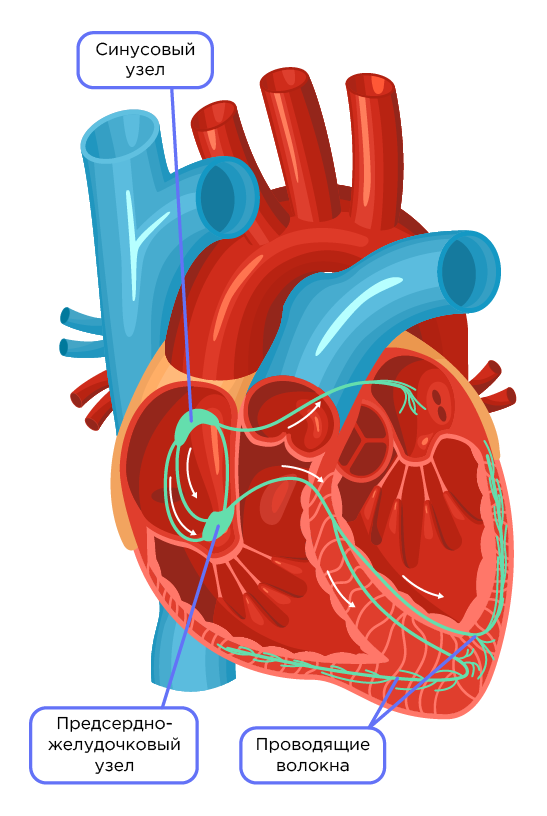

Свойства мышц человека: Основные характеристики

Раздел: Объективный взгляд